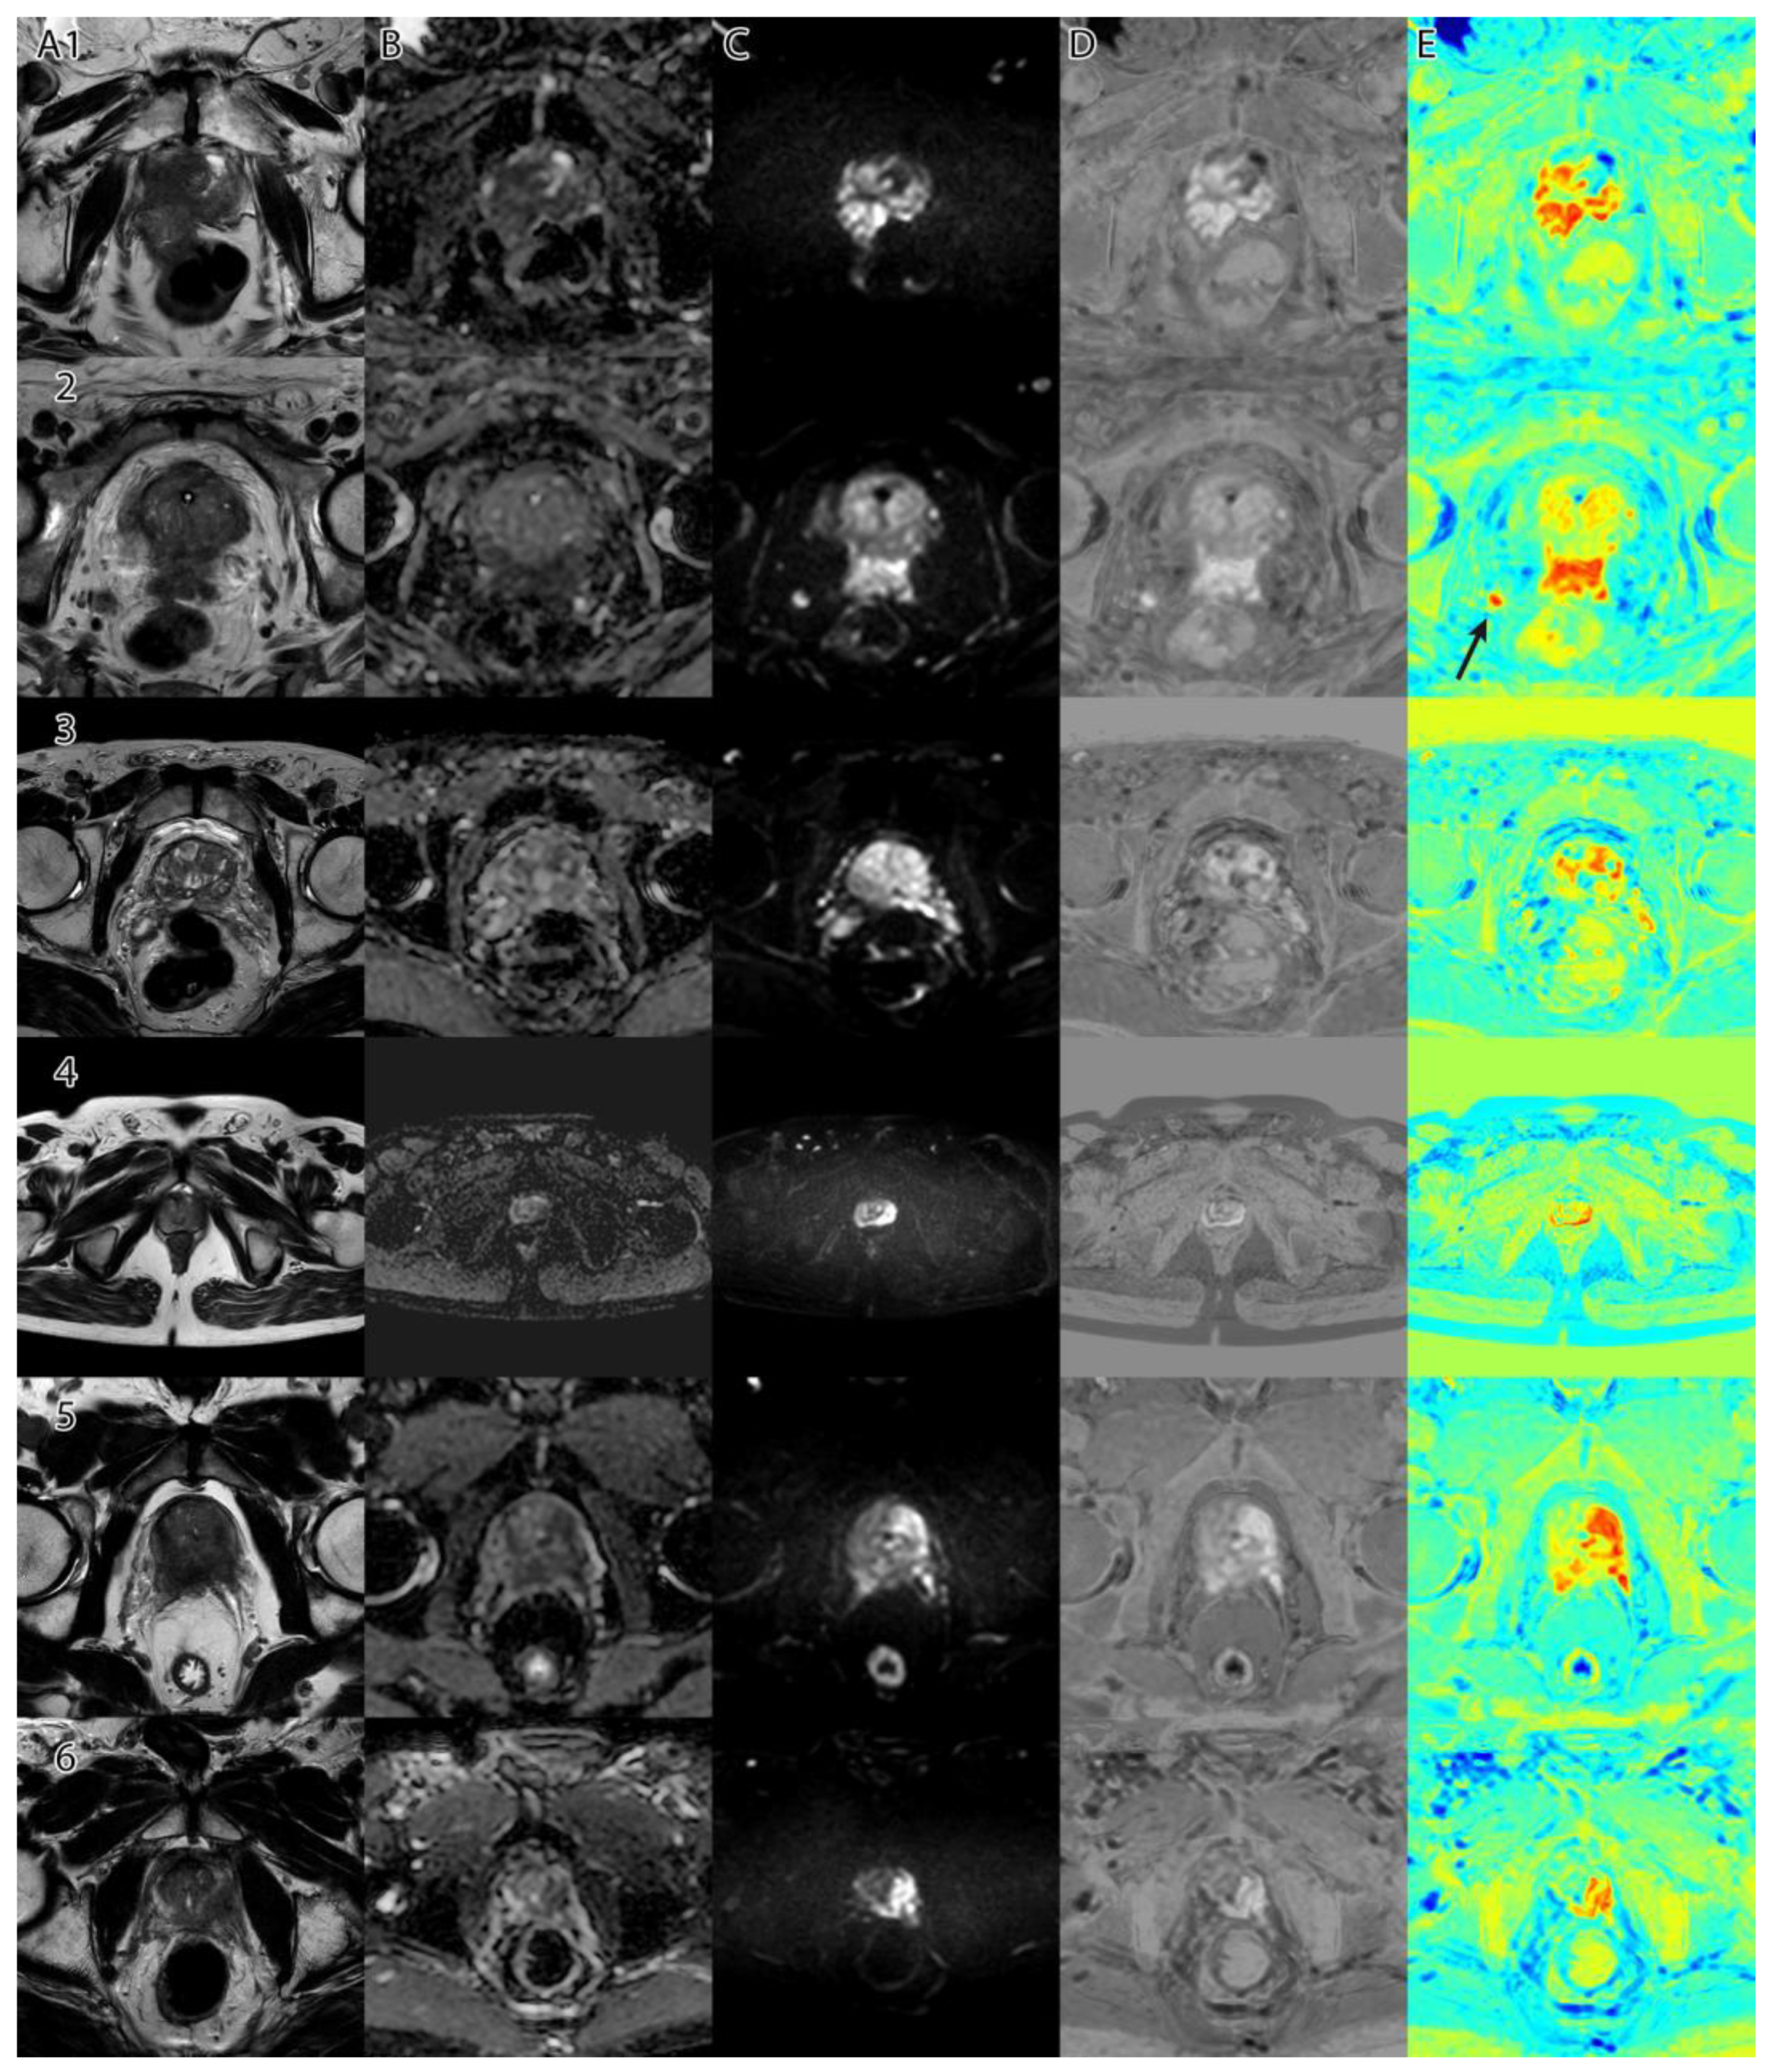

Samples of the computed tumor intensity images can be seen in Figure 2 for a PI-RADS 2 patient and in Figure 3 for a PI-RADS 5 patient. Notice the difference in “jet” intensity between the control patient and the patient with extraprostatic invasion.

Figure 6 shows a collage of several cases and the resulting tumor intensity mask. The overlap between the PI-RADS class intervals and the original dataset can be seen in Figure 7. Using the empirically selected thresholds, we obtained 100 percent accuracy in identifying the PI-RADS 5 class on the images.

As seen in Figure 6, column D, when adding a ‘jet’ color map to the algorithm’s tumor intensity output, the highlighted zones appear in red and orange, while the less suspicious zones are colored in yellow. Non-tumoral surrounding tissue has colors ranging from green to blue.

As seen in Figure 6, image E2, the method is consistent and identifies high-risk lesions outside the prostatic area (see right side nodule in red (arrow)). The nodule was later confirmed through biopsy to be high-grade tumor prostate adenocarcinoma invasion.

Figure 6. Collage of several cases and the resulting tumor intensity mask: (column A)—T2WI; (column B)—ADC; (column C)—DWI; (column D)—tumor intensity mask (grayscale); (column E)—tumor intensity mask with ‘jet’ color map. E2—Arrow shows a high risk of extraprostatic invasion of nodules.